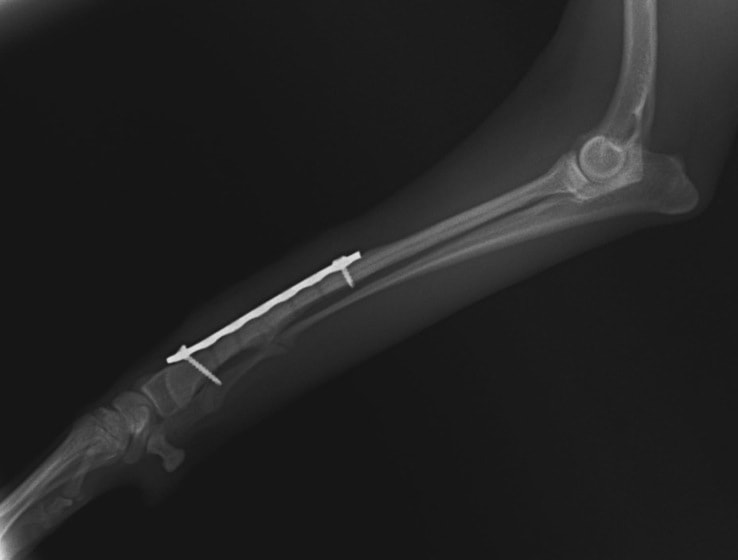

他院にて左大腿骨遠位の成長板骨折(salter-harrisⅠ型)が認められており、治療相談を目的として来院。当院にて、キルシュナーワイヤーを用いたピンニングにより骨折部位の整復を行いました。術後の経過は良好で、現在も経過観察中です。

術後レントゲン

Arthrex社のターゲティングデバイスを用いてピンニングの位置を調整することで、確実な固定を行っています。当院ではこの手術器具以外にも、人の手術にも使用される様々な器具を導入し、手術精度を高め、また医療メーカーと新しい器具の開発、試作にも取り組んでおります。